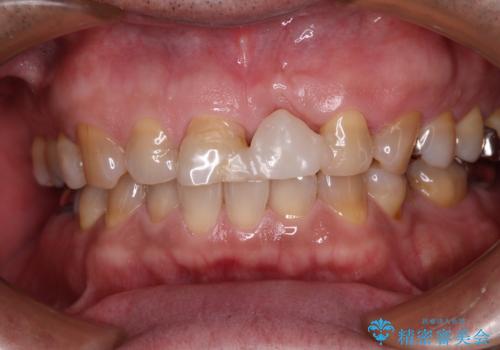

歯肉移植術による更なる歯肉ラインの改善も検討しましたが、笑ったときに歯肉ラインは唇に隠れてしまうため、現在の位置にて仕上げることとしました。

骨の前後幅が小さかったため、細いインプラントを選択せざるを得ない状況でした。咬合力が非常に強い方のため、就寝時のマウスピース装着を徹底していただき、インプラントへの負担を軽減することとしています。